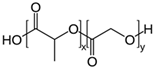

| Polylactides (PLA), polylactic-co-glycolic acid (PLGA), polyglycolides (PGA) |  , ,  | Sol-gel/solvent casting | Propranalol, Exxon Chemical Co. | Good biocompatibility; lactic and glycolic acids are the degradation products and they are easily eliminated from the body | [161,162] |